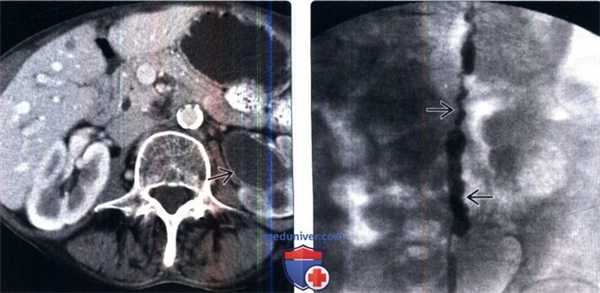

(Слева) КТ мочевого пузыря без контрастирования, аксиальный срез: два плотных кальцинированных конкремента в области левого МПС.

(Справа) Аксиальная проекция того же среза, полученная в отсроченную урографическую фазу: конкременты находятся внутри уретероцеле. Иногда дифференциальная диагностика между врожденным уретероцеле, содержащим камни и приобретенным расширением терминального отдела мочеточника при обструкции конкрементом (так называемое «певдоуретероцеле») может представлять трудность.